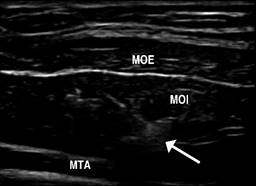

Ultrasonido terapéutico en pared abdominal

Con ayuda de equipos de ultrasonido portátiles es factible realizar en quirófano bloqueos anestésicos que contribuyen a disminuir el dolor posoperatorio y permitir incluso algunos procedimientos como las plastías inguinales abiertas bajo anestesia local y sedación, las plastías de hernias umbilicales y de la línea media. El bloqueo del plano del transverso abdominal30 se emplea colocando el transductor en el flanco en un plano axial, en el punto medio de la distancia entre la cresta iliaca y el borde costal inferior. Se identifica con el transductor la imagen de los músculos del componente lateral y, empleando una dilución de bupivacaína o ropivacaína, se introduce la aguja bajo guía sonográfica hasta que se identifica la penetración de los dos músculos oblicuos y se infiltra justo entre el oblicuo interno y el músculo transverso abdominales (Figura 8). Este procedimiento produce un bloqueo que puede abarcar desde los dermatomas T9 al L1. Su principal utilidad es la disminución del dolor posoperatorio y, por lo tanto, puede aplicarse en toda cirugía abdominal. Adicionalmente, para un mayor efecto analgésico/anestésico, se realiza un bloqueo de la vaina de los rectos, colocando el transductor en sentido axial a nivel del epigastrio, en el borde lateral de cada músculo recto y se infiltra delante de la vaina aponeurótica posterior. La combinación bilateral de estos dos procedimientos (bloqueo del plano transverso y de la vaina de los rectos bilateral) puede emplearse en toda cirugía abdominal, lo que reduce significativamente el dolor posoperatorio. En las plastias inguinales abiertas se emplea el bloqueo de los nervios ilioinguinal e iliohipogástrico, más anestesia local en el sitio de la incisión. Todos estos procedimientos pueden también utilizarse en el consultorio, para tratar dolores inguinales o de pared abdominal, en casos de pacientes con problemas de dolor crónico posoperatorio o con lesiones deportivas, combinando el anestésico local con agua inyectable y un esteroide de depósito como, por ejemplo, 5 mg de betametasona. Pueden beneficiarse de bloqueos repetidos con intervalos de 15 días (sin repetir necesariamente el esteroide combinado en cada bloqueo). Tratándose de la infiltración de la toxina botulínica, como parte de una preparación preoperatoria de hernia compleja,31 se aplica la misma técnica de guía sonográfica en el plano axial del flanco abdominal para inyectar la toxina, bajo visión directa de los músculos del componente lateral del abdomen. En ese caso empleamos la guía con ultrasonido, aplicando cinco punciones por flanco, para asegurar que se deposite la toxina mayormente a nivel del músculo oblicuo interno.

Figura 8: Ecografía de los músculos del componente lateral a nivel del flanco: músculo oblicuo externo (MOE). Músculo oblicuo interno (MOI). Músculo transverso (MTA). La flecha muestra la entrada de la aguja durante el bloqueo del plano transverso. Ropi: lago de anestésico local (ropivacaína) mientras es infiltrado entre MT y MOI.